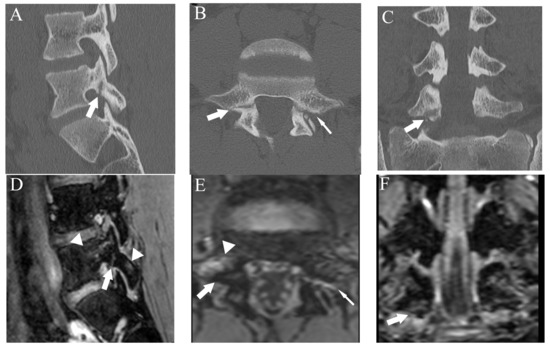

Figure 5.

Comparison of bilateral grade 3 fractures at L5 from an 11-year-old male in multiple planes between CT and DESS. (A–C) CT shows complete fractures in L5 pars interarticularis on the right-sided sagittal, axial, and coronal plane, respectively (arrows). (D–F) DESS shows comparable complete fracture on the right-sided sagittal, axial, and coronal plane, respectively (arrows).

Figure 6.

Comparison of grade 2 fracture at the right pars interarticularis at L5 from a 14-year-old male in multiple planes between CT and DESS. (A–C) CT shows grade 2 fracture on the right pars interarticularis on the right-sided sagittal, axial, and coronal plane, respectively (arrows). On the axial plane, fracture of the left side is also delineated (thin arrow). (D–F) DESS shows grade 2 fractures comparable to CT on the right-sided sagittal, axial, and coronal plane, respectively (arrows). The sagittal and axial images delineate BME around the fracture (arrowhead), and the left pars interarticularis fracture is also delineated on the axial image (thin arrow).